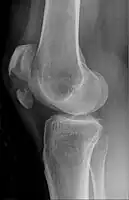

| Patella fracture | |

| A fracture of the patella seen on a lateral view | |

| Diagnostic method | Based on symptom, confirmed with X-rays.[3] |

It typically results from a hard blow to the front of the knee or falling on the knee.[1]The patella can also be fractured indirectly. For example, a sudden contraction of the quadriceps muscle in the knee can pull apart the patella.[1]Diagnosis is based on symptoms and confirmed with X-rays.[3] In children an MRI may be required.[3]

Diagnosis is based on symptoms and confirmed with X-rays.[3] In children an MRI may be required.[3]